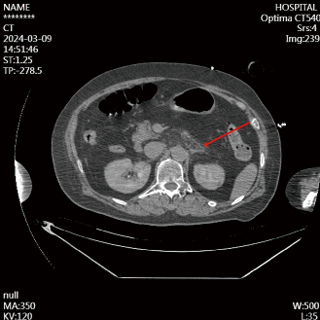

入院查下肢静脉彩超:双下肢深静脉血栓;心脏彩超:右房扩大(横径41 mm),右室扩大(前后径30 mm),三尖瓣中量反流;脑CT:脑萎缩;肺动脉CTA:左、右肺动脉及分支内多发栓塞;胸部肋骨CT:左侧第2~8肋骨、右侧第1~7肋骨骨折、双肺下叶炎症;腹部CT:胰体部下方片絮状渗出影(见图 1)。D二聚体5.26 mg/L;动脉血气分析pH 7.405,二氧化碳分压35.5 mmHg,氧分压46.2 mmHg,血乳酸2.4 mmol/L,血氧饱和度79.9%,剩余碱-2.56 mmol/L,实际碳酸氢根21.7 mmol/L;血脂、血清淀粉酶及脂肪酶正常;肝肾功能正常。

| 图 1 2024-03-09患者胰腺形态、大小及密度未见明显异常,胰体部下方见少许片絮状渗出影 |

首先,本例患者发病前无腹痛腹胀、恶心呕吐等消化道症状,无高脂血症、饮酒等常见病因,无基础胆道结石病史,缺乏AP典型的症状及病因;其次,本例CA患者入院TTM及镇静治疗,由于沟通条件受限,通过腹部触诊判断患者的疼痛反应存在客观性难度;另外,血清淀粉酶及脂肪酶指标正常,缺乏AP的胰酶诊断条件,腹部CT胰腺形态、大小及密度正常,尽管提示胰腺下方有少量渗液(图 1),但临床未予以足够重视,早期漏诊AP。